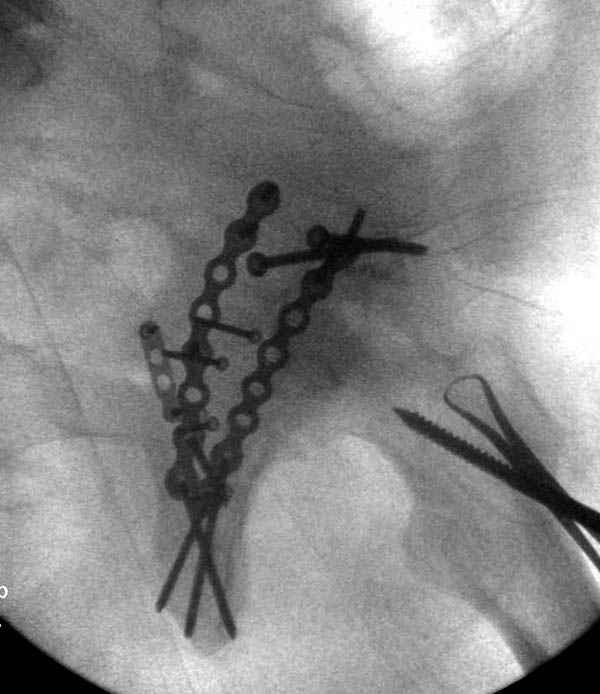

На седьмой день зафиксирован перелом ацетабулума через задний доступ. Перед операцией для профилактики DVT, IVC фильтер, также получает Lovenox.

Там множество обычных 2.7 мм шурупов, потом идет фиксация основными пластинами.

Снимки здесь....